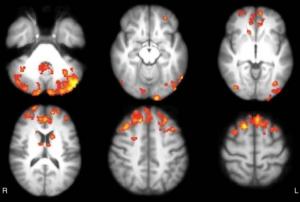

La connectivité fonctionnelle est réduite (visuel ci-contre) chez les patients atteints de sclérose en plaques, mais jouer à des jeux vidéo « cérébraux » peut rétablir une partie e cette connectivité «et finalement contribuer à améliorer certaines capacités cognitives en renforçant la plasticité cérébrale. C’est la démonstration d cette étude de l'Université Sapienza (Rome), publiée dans la revue Radiology.

Ø les 12 patients du groupe programme vidéo ont enregistré des hausses significatives de connectivité fonctionnelle thalamique, dans les zones du cerveau correspondant au réseau en mode par défaut, l'un des réseaux cérébraux clés impliqués dans la cognition.

Les résultats montrent une amélioration significative de la plasticité, ou de la capacité du cerveau à former de nouvelles connexions. « Cette connectivité accrue traduit le fait que le programme vidéo a modifié le mode de fonctionnement de certaines structures cérébrales » , explique le Dr De Giglio, auteur principal de l'étude. En effet, on constate une amélioration significative dans les résultats des tests évaluant l'attention et les fonctions exécutives, les compétences cognitives de niveau supérieur.